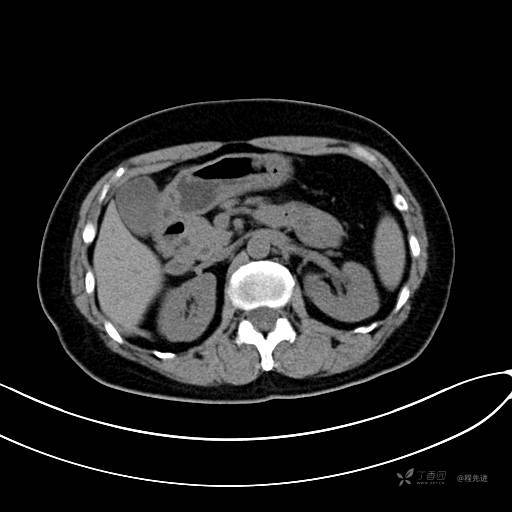

CT增强动脉期